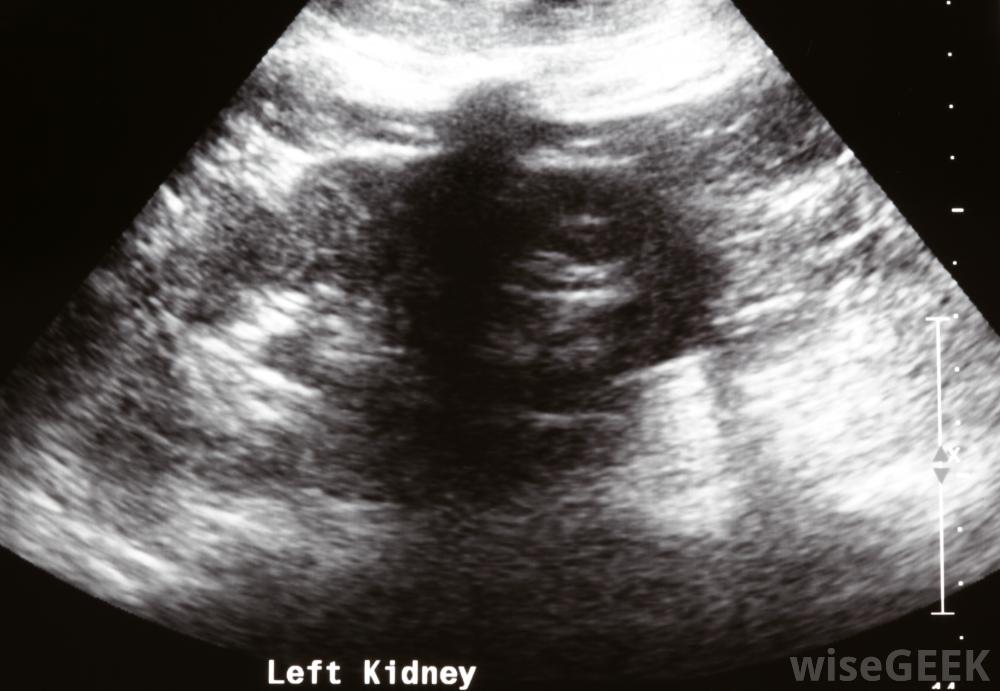

护士通常会在场监督患者生命体征,以及疼痛和焦虑程度。医务人员,通常是放射科医生,将使用x光或超声波来定位肾脏。此时,一根针直接穿过皮肤的所有层插入肾脏。x射线染料通过针头插入以帮助插入导尿管。导管被插入肾脏,有时在长时间保持原位时用针固定

在肾造口术中,超声用于指导插管。